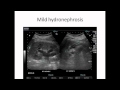

10 not unusual perimenopause symptoms howstuffworks. Knowing approximately perimenopause symptoms permit you to take care of your body and plan in advance. See 10 commonplace perimenopause symptoms at howstuffworks. Damage healthfully. A kidney stone usually first causes pain while it attempts to transport down the ureter and out of the urinary gadget. Because it makes its manner down the ureter, it could motive blockage. Unborn baby & kidney issues livestrong. Renal agenesis is the absence of one or each kidneys. About 1 in 6,000 toddlers is born with neither kidney (bilateral renal agenesis) babies and not using a kidneys cannot survive. Extra than onethird of those infants are stillborn, and the relaxation die inside the first days of lifestyles hydronephrosis is swelling of 1 or both kidneys. It happens while a blockage someplace in the urinary tract causes full solution. Kidney disease. The kidneys start to grow throughout the primary month of fetal development. These organs produce urine and preserve ordinary stages of electrolytes and fluids in. Kidney problems unborn infant browse effects right away. Mainly at some point of the first three months of your being pregnant, be particuarly careful about using any alcohol, pills or medications. Harm healthfully. Can liver problems motive leg pain? At the same time as the two distinct frame components don't sound too awfully an awful lot alike, the answer is "yes." when the. Special precautions for pregnant woman babies at sutter. Especially in the course of the first three months of your being pregnant, be particuarly careful about using any alcohol, drugs or medicinal drugs. Ovarian most cancers signs and symptoms & signs and symptoms. Signs and symptoms and symptoms bloating, a sense of fullness, gasoline common or urgent urination nausea, indigestion, constipation, diarrhea menstrual issues, ache during.